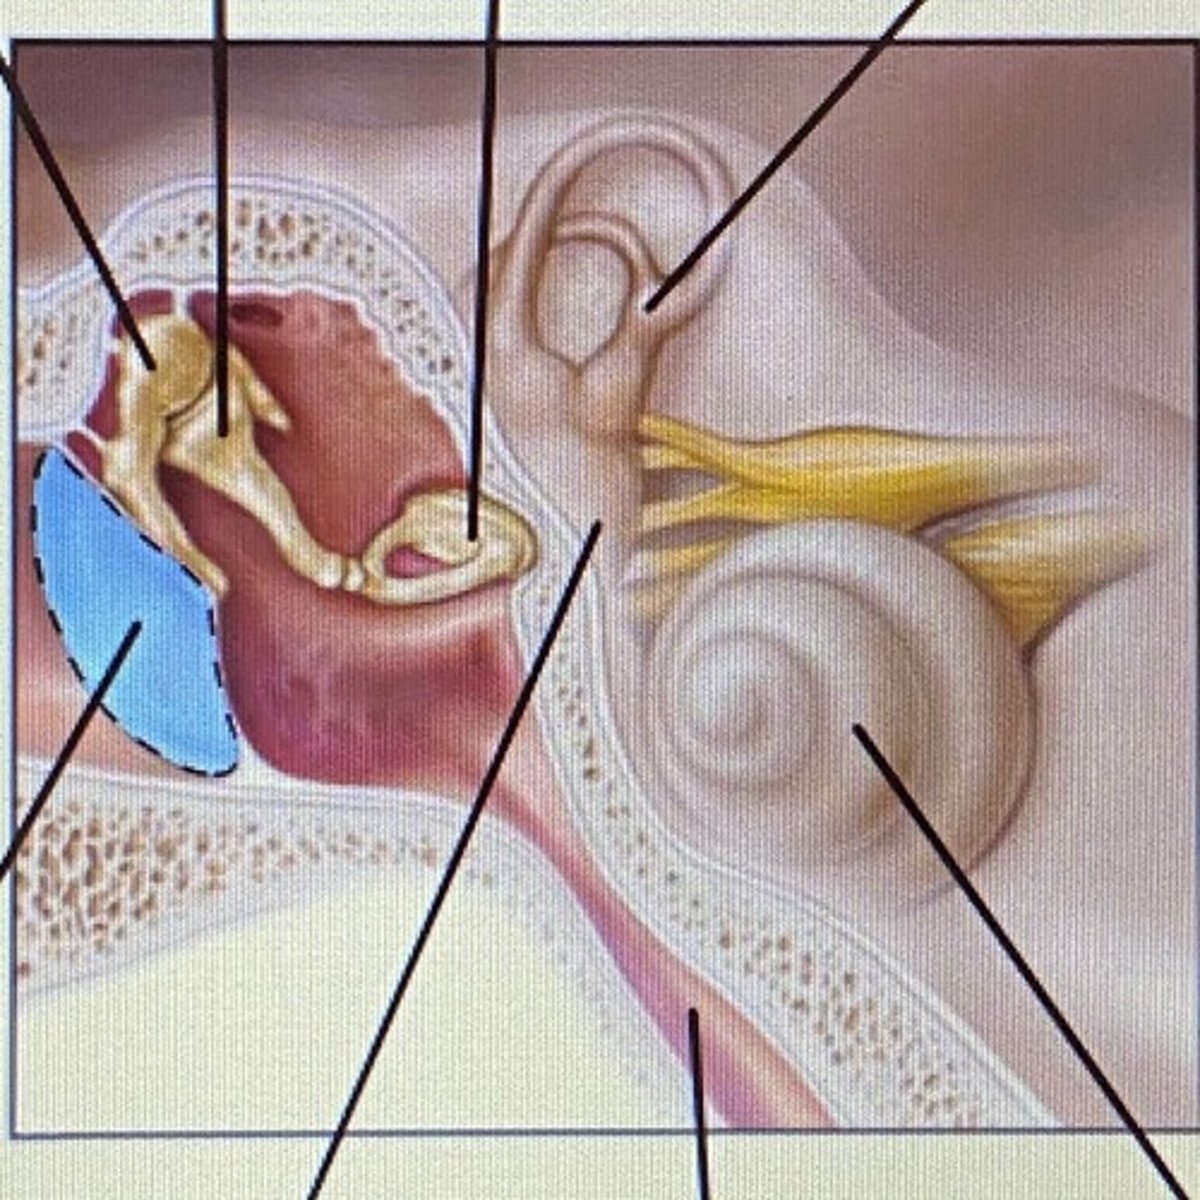

auricle

External Acoustic Meatus

vestibule

-functions in balance and equilibrium

Vestibulocochlear Nerve

- cranial nerve 8

Stapes

Incus

Malleus

Tympanic Membrane

pharyngotympanic tube

external ear

middle ear